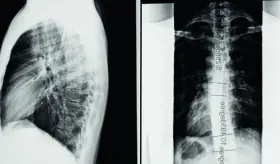

La lumbalgia o dolor lumbar bajo, representa hoy una de las principales causas de discapacidad a nivel mundial.